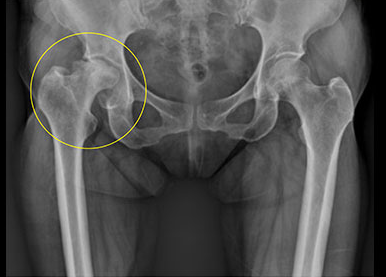

대퇴골두 무혈성 괴사는 대퇴골두라는 몸의 큰 뼈의 꼭대기 부분이 혈액 공급이 차단되어 뼈세포가 괴사하는 상황을 말합니다. 이 질환은 대퇴골의 극히 작은 부분에서 발생하며, 일반적으로 외상, 골절, 음주, 스테로이드 약물 등이 원인으로 알려져 있습니다. 하지만 정확한 원인은 아직까지 밝혀지지 않았습니다.

대퇴골두 무혈성 괴사는 비교적 젊은 연령층에서 발생할 수 있는 드문한 질환 중 하나입니다. 병의 진행이 진행될수록 인공관절 치환술이 유일한 치료법이 되기 때문에 초기 발견과 적절한 관리가 매우 중요합니다.

대퇴골두의 모양이 유지되는 초기에는 약물치료와 재활운동을 통해 병의 진행을 지연시킬 수 있습니다. 하지만 대퇴골두가 심하게 손상된 경우 고관절 인공관절 수술이 필요할 수 있습니다.